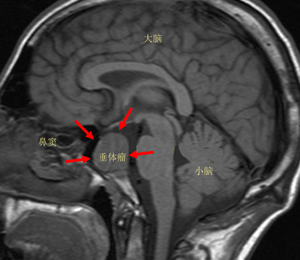

位于我们人体大脑的丘脑下部,有一卵圆形小体,医学上称之为垂体。垂体瘤是一组从垂体前叶和后叶及颅咽管上皮残余细胞发生的肿瘤,是良性腺瘤。其主要表现为头痛、视力障碍、内分泌障碍,三者统称垂体瘤三联症。

垂体仅占大脑体积的1/1000,看似微不足道,却是人体神经内分泌的最高指挥中心,分泌5种主要神经递质和激素,使全身内分泌系统的激素保持在一个平衡状态。一旦垂体分泌神经递质的机能发生紊乱,整个内分泌系统就会崩溃,过度分泌便形成了垂体瘤。